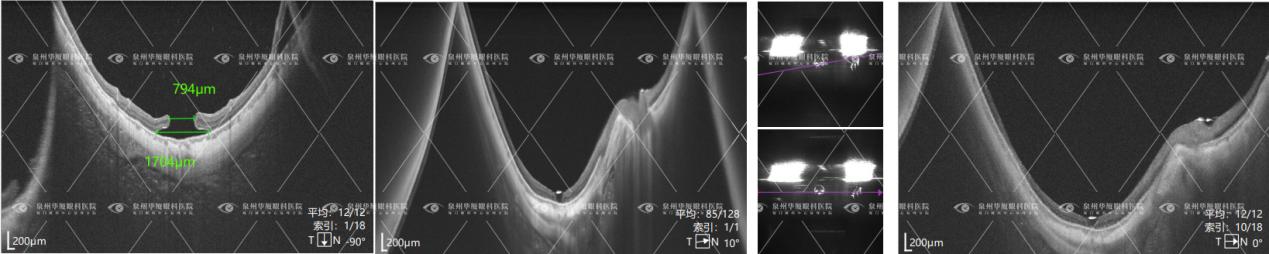

历经一个多小时手术,李勇院长及团队凭借丰富的经验和默契配合,克服了患者眼部瘢痕粘连、组织结构紊乱等难题,成功完成视网膜复位与裂孔封闭。术后12小时复查右眼OCT显示:患者黄斑区两个裂孔闭合、视网膜复位良好(下图5);目前患者右眼视力逐步恢复中。

(图5 欧堡、oct检查报告)